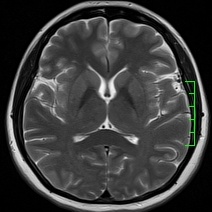

磁共振——锁定“水”的科技

磁共振(MRI)与普通X线、CT不同,不依赖于X线成像,而是氢原子核,也可以理解为水。以前称为核磁共振,是因为MRI的原理是用较大的磁场,使人体内原本随意排列的氢原子核磁场的磁力线方向统一,再突然把磁场的作用去掉,监测其中信号的变化。MRI成像依靠不同组织含氢核数目不同,或者可以近似理解为不同组织含水量不同,形成图像差异,来区别组织。所以MRI对中枢神经系统和软组织有着良好的分辨能力,适用于软组织、神经系统疾病、内脏器官,并且多序列及多参数成像、功能成像。不过,MRI检查时间较长,价格较贵,预约时间较长。

磁共振平扫图像